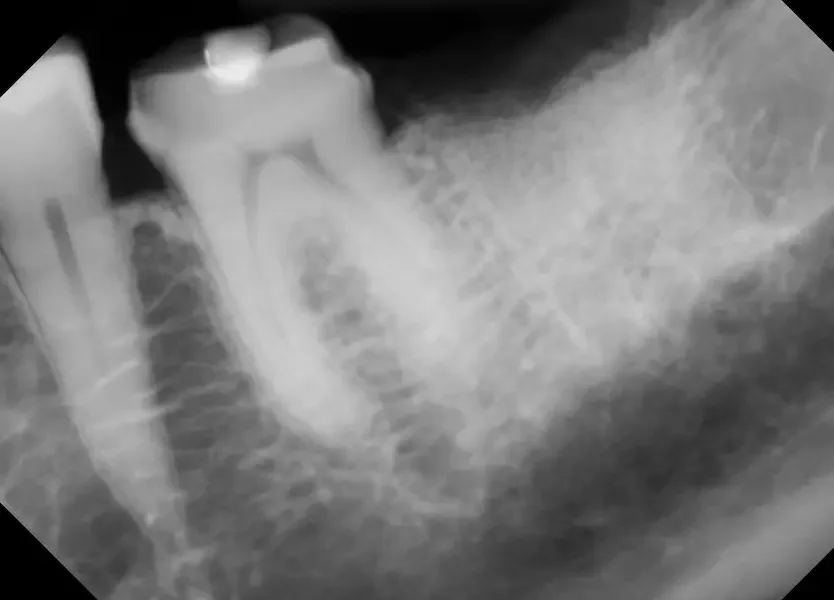

Before removing the tooth, we assessed bone health and root position with detailed imaging. In this case, the tooth had a prior root canal and a cavity on the back side, which caused the crown to loosen and eventually fall off. This tooth could not be saved by a new crown, so it needed to be extracted to prevent risk of infection and further damage of surrounding tissue. After reviewing alternative options, this patient is planning on a future dental implant to restore the site.

X Ray of tooth #18 Prior to Extraction

✅ Purpose: understand root formation, nerve anatomy, and ensure the socket walls are intact for grafting.